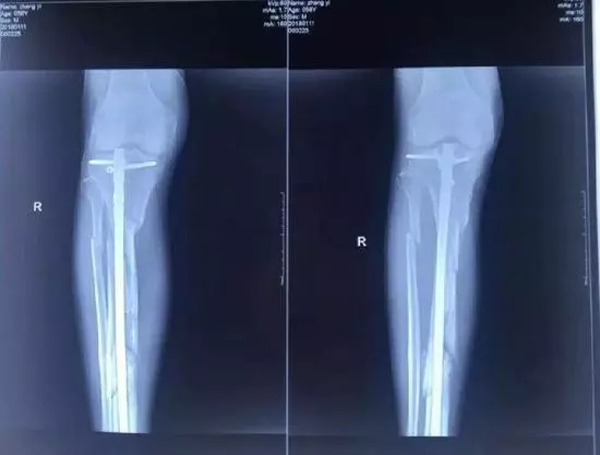

他興辦的廊坊市城南骨科醫(yī)院發(fā)展得越來越好,引起了原本是小股東的楊玉忠對(duì)醫(yī)院的覬覦。股東如果想要擴(kuò)大股權(quán),有許多正常的途徑,用合理合法的方式完全可以實(shí)現(xiàn)。但楊玉忠卻采取了最直接卻也最暴力的方式,不斷用欺騙、騷擾、干預(yù)人事等方式排擠張毅,使他在專心看病的同時(shí),疲于應(yīng)付,心理壓力極大,甚至在2017年10月18日,張毅被四名駕駛無牌豪華越野車的黑衣人打斷腿骨。即使是如此,當(dāng)?shù)睾趷簞?shì)力依然沒有放過張毅,不僅舊醫(yī)院被掏空占據(jù),新醫(yī)院也無法開張,200多醫(yī)護(hù)人員面臨衣食無著的困境。雖多方求助,對(duì)方依然逍遙法外,最終逼死了張毅。

資料圖